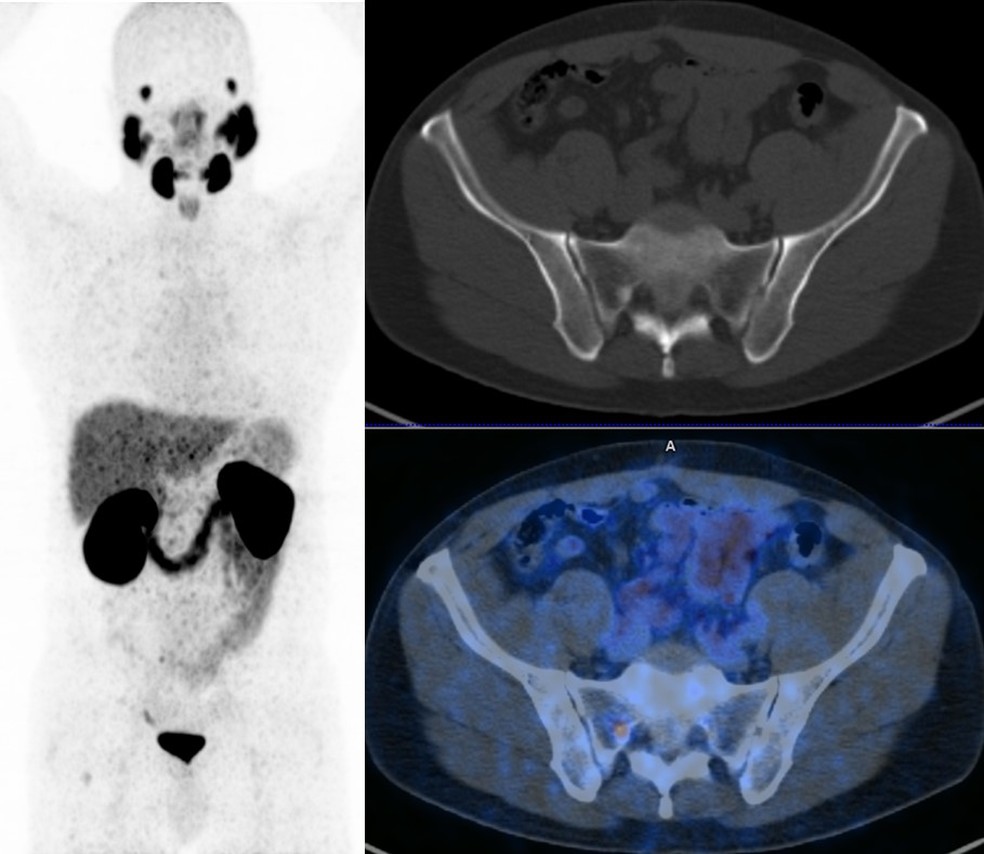

PET PSMA de paciente com recidiva bioquímica (PSA=0,5 ng/mL) mostra discreta metástase óssea na pelve. — Foto: Divulgação

O PET PSMA (do inglês antígeno de membrana específico da próstata) é um exame que utiliza uma medicação radioativa de baixa dose com afinidade específica para a proteína de membrana fabricada em abundância pela célula do câncer de próstata. O exame possibilita determinar onde o câncer se encontra e se este já se espalhou para outros órgãos. O PET PSMA tem um extraordinário potencial diagnóstico porque é mais sensível e mais específico do que os exames de imagem convencionais mais utilizados, como a tomografia computadorizada e a cintilografia óssea. Atualmente, o PET PSMA com gálio vem sendo usado no Brasil e, assim como na Alemanha e Austrália, já demonstrou um alto impacto na mudança da conduta terapêutica de pacientes com câncer de próstata.

As indicações para o exame de PET PSMA incluem a avaliação de recidiva bioquímica (quando os níveis de PSA encontram-se acima de 0,5 ng/mL após prostatectomia radical ou acima de 2,0 ng/mL após radioterapia pélvica), diagnóstico inicial quando o exame de ressonância magnética não é esclarecedor, estadiamento inicial (antes do tratamento primário) em pacientes de alto risco (por exemplo PSA > 20 ng/mL; Gleason > 7) e no planejamento de radioterapia.